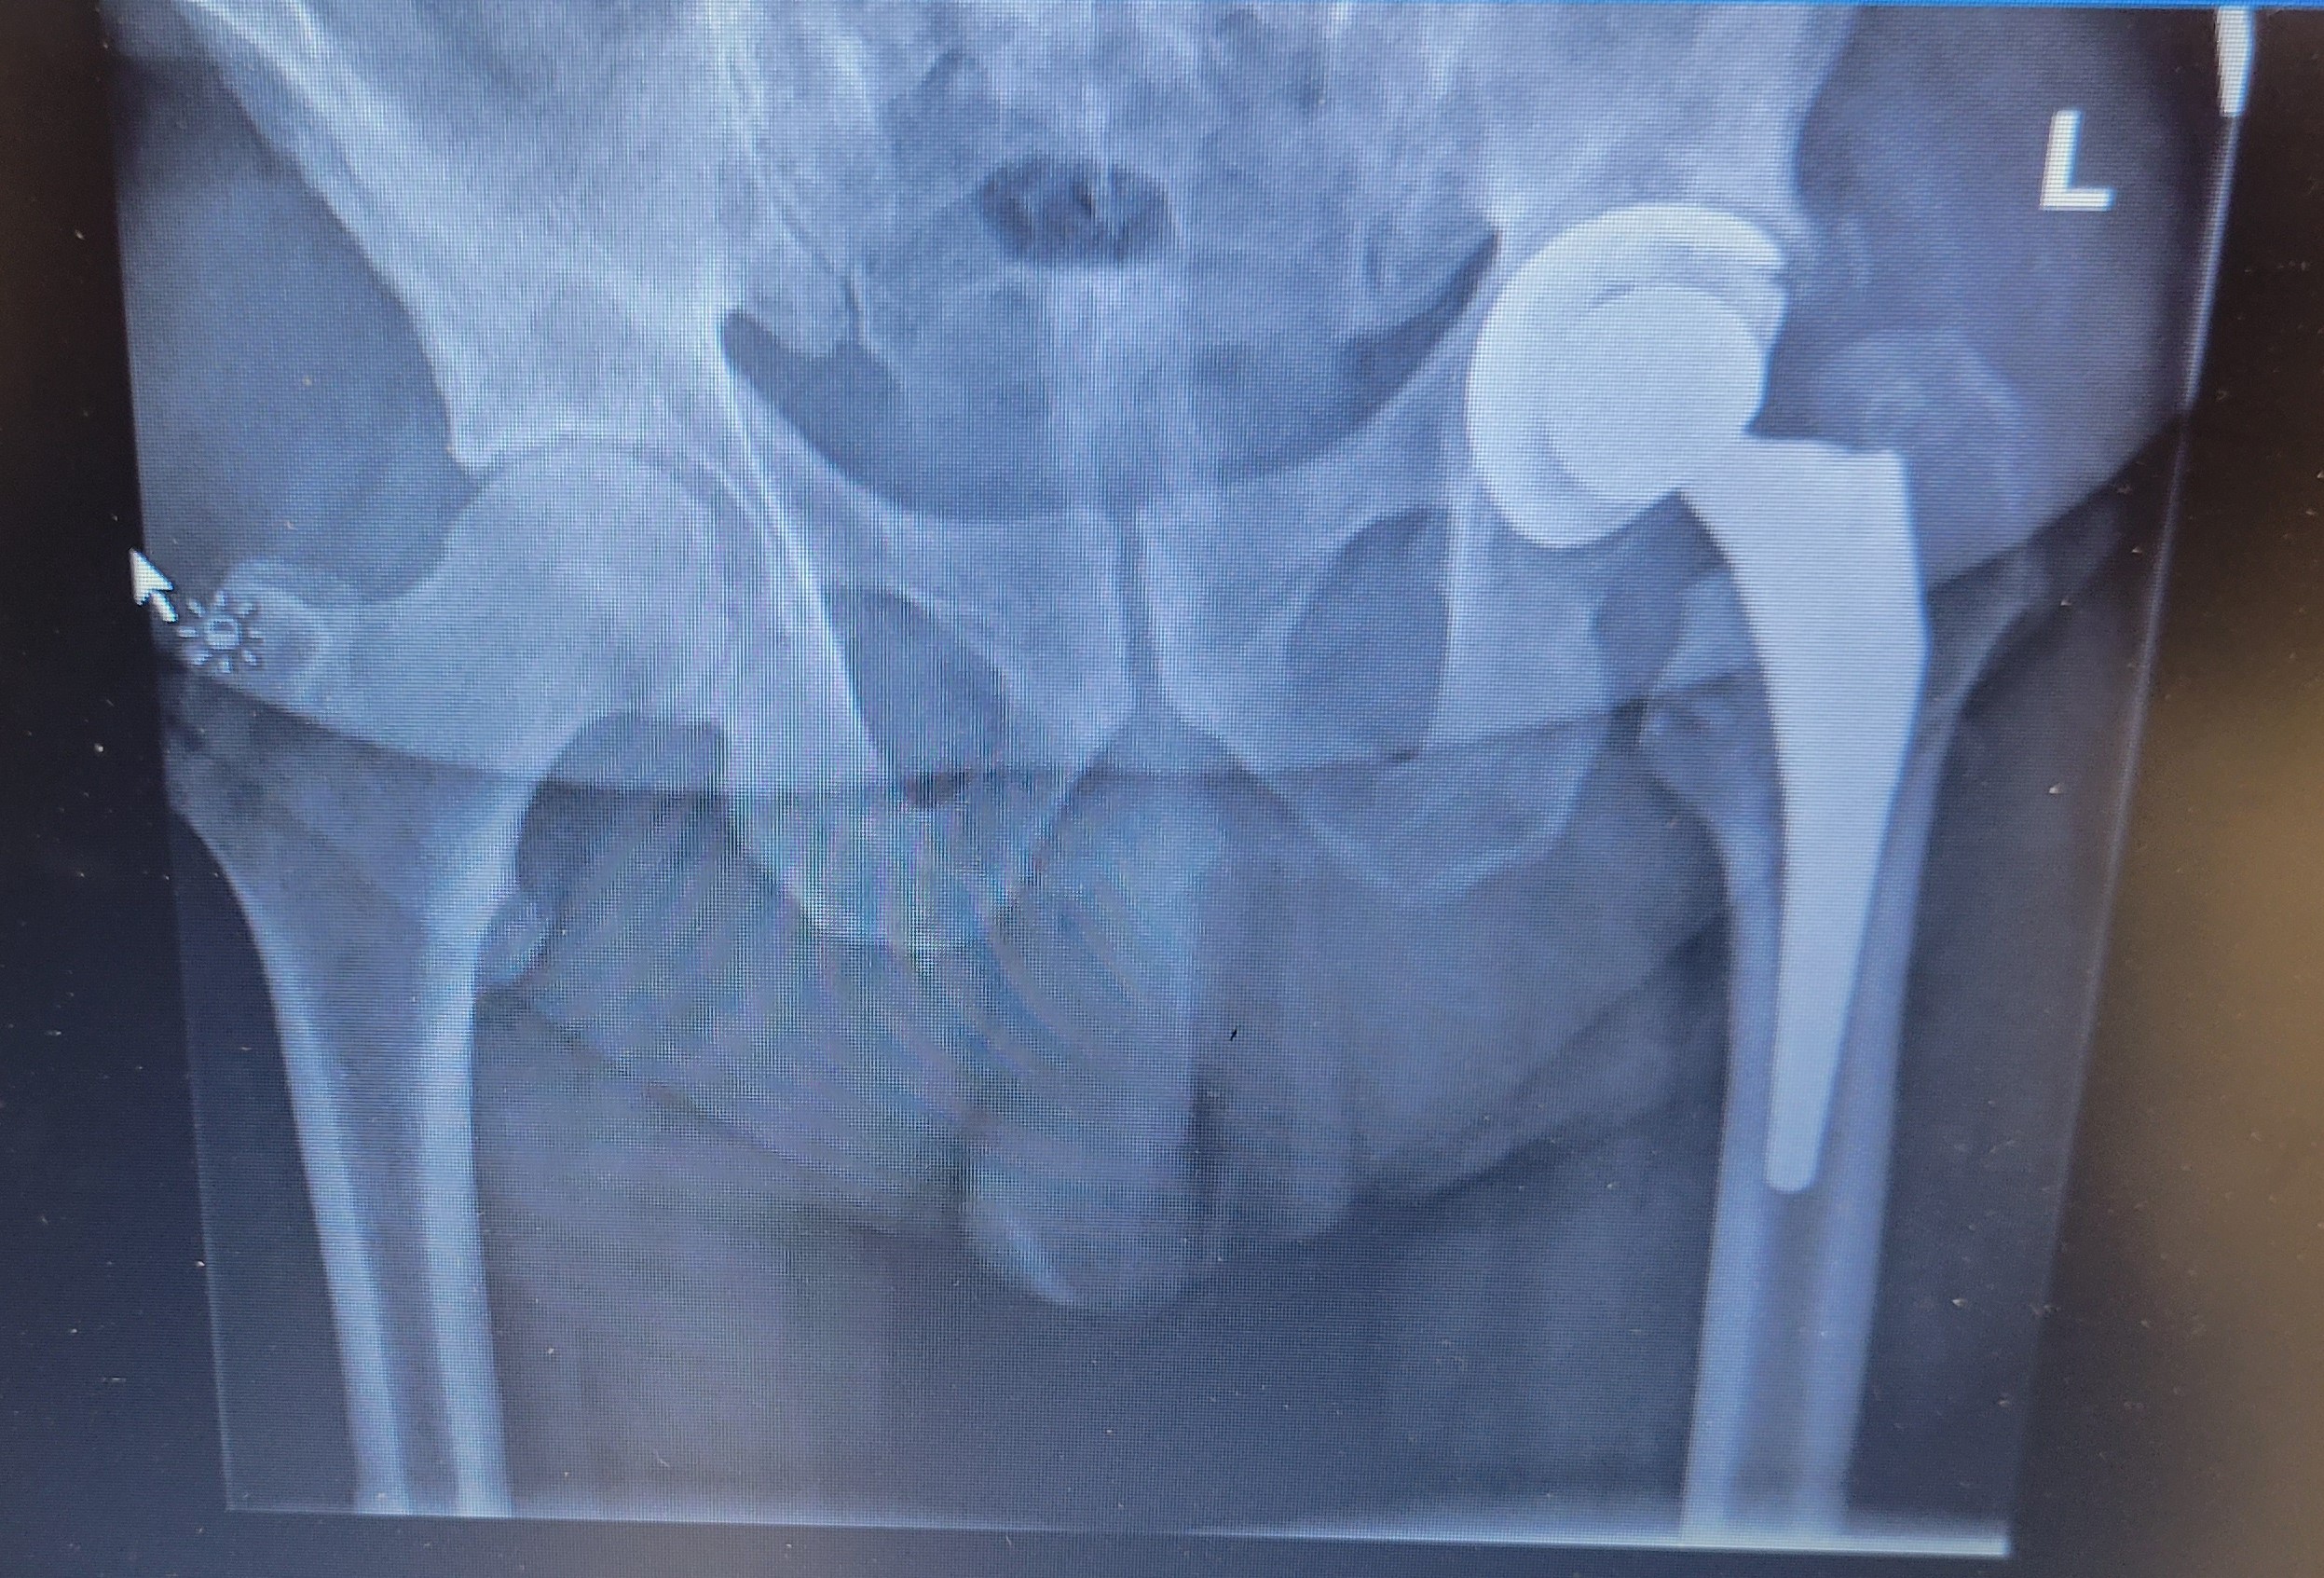

- Perhaps because my body is not always happy about the way I’ve treated it over the years. And yes, I am honest about that, I’ve not always been the best caretaker. As well there are a couple of things which are hereditary. I was diagnosed with gout around thirty years ago, and although I’ve been on medications since then, it has contributed to arthritis in different parts of my body, leading to a hip replacement two years ago.